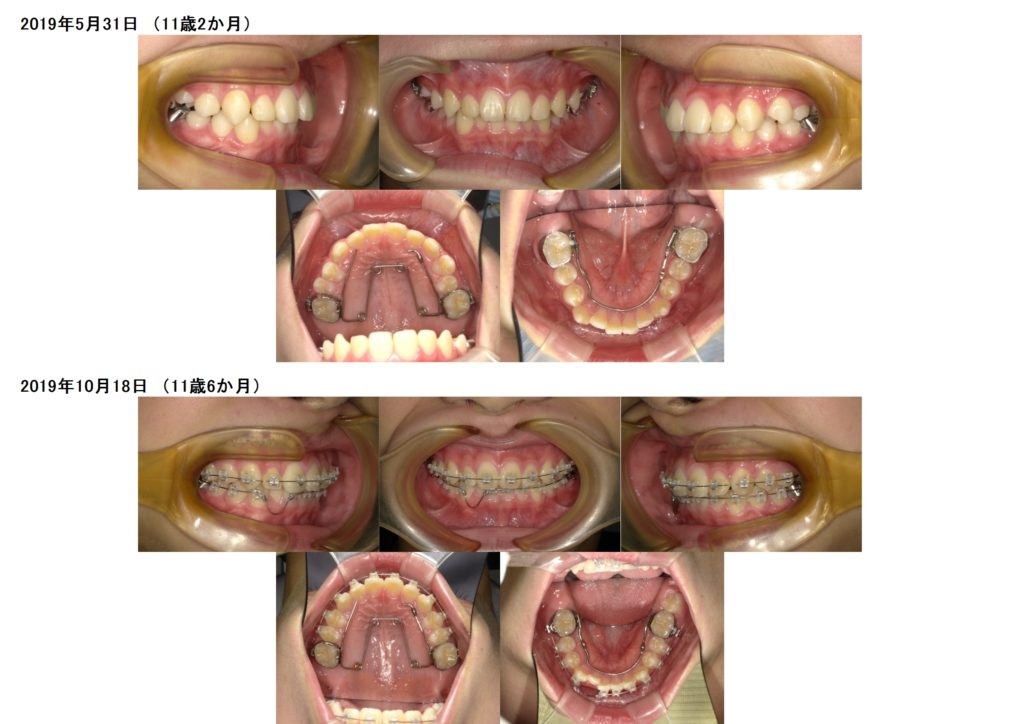

↑その後、スペースが確保でき上下フルブラケット装置を着けました。

↑調整を繰り返し、、、、